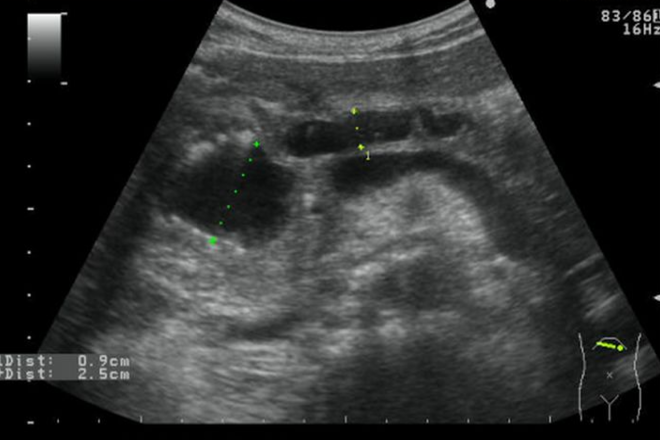

Enfermedades del Bazo

El bazo está situado en el abdomen, a la izquierda del estomago en el área de hipocondrio izquierdo, bajo las costillas y es un órgano esencial para el buen funcionamiento de nuestras defensas. Un mal funcionamiento del bazo puede además ocasionar alteraciones digestivas, hemorragias, anemia, detención de líquidos, diarreas, entre